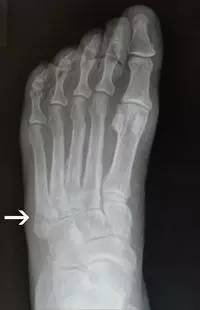

14.第五跖骨骨折

第五跖骨基底部骨折的不同类型:Stress 骨折;Jones 骨折:第五跖骨基底部以远 1 英寸内的骨折称为 Jones 骨折;Avulsion 骨折。

(来源:Radiopaedia)

Stress 骨折(来源:OrthoInfo-AAOS)

Jones 骨折正位片(来源:Radiopaedia)

Jones 骨折斜位片(来源:Radiopaedia)

第五跖骨骨折还有 dancer’s fracture。

dancer’s fracture 正位片(来源:footEducation)

dancer’s fracture 侧位片(来源:footEducation)